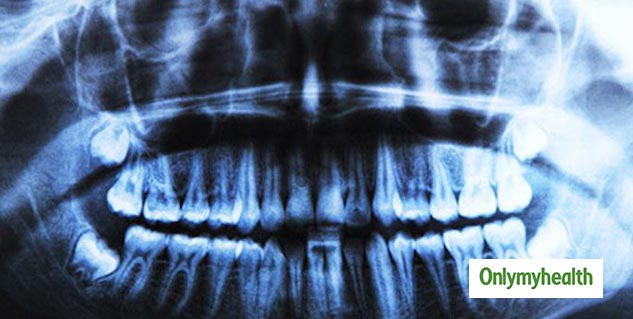

एक्स-रे

आप जब अपने डेंटिस्ट के पास जाते हैं तो वह एक्स-रे करने से पहले आपको एक कंबल से कवर देता है। इसका एक मुख्य कारण यह होता है कि एक्स-रे की वजह से आपको कैंसर होने की संभावना को अधिक बढ़ाता है। एक्स-रे की रेडिएशन (Radiation) की मात्रा जितनी अधिक होगी कैंसर होने का जोखिम भी उतना ही अधिक होगा। लेकिन अभी तक यह पता नहीं चल पाया है कि रेडिएशन (Radiation) कितनी मात्रा सुरक्षित है। यही कारण है कि ईपीए (EPA) की अपनी सीमा है कि आप इसके कितनी मात्रा में ले सकते हैं।